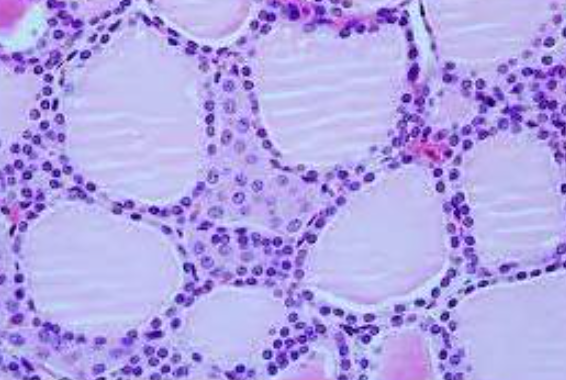

Tecido adiposo multilocular

Tecido adiposo unilocular